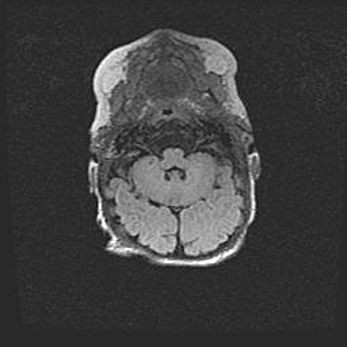

Подострая гематома правой гемисферы мозжечка.

Наружная гидроцефалия.

Возраст: 15 дней

Вес: 3100 г

Пол: женский

Окружность головы: 37 см

Срок гестации: 35-36 недель

При открытой наружной форме гидроцефалии у новорожденных расширяются и переполняются субарахноидные пространства.

Кровоизлияния в мозжечок имеют две клинико-анатомические формы: полушарные гематомы и кровоизлияния в червь.

К появлению этой патологии может привести: повреждения головного мозга, возникающие в результате асфиксии и гипоксии плода при беременности, или травмы во время родов. Редко гематома мозжечка может быть результатом первичной коагулопатии и сосудистой мальформации, диссеминированном внутрисосудистом свертывании, изоиммунной тромбоцитопении.